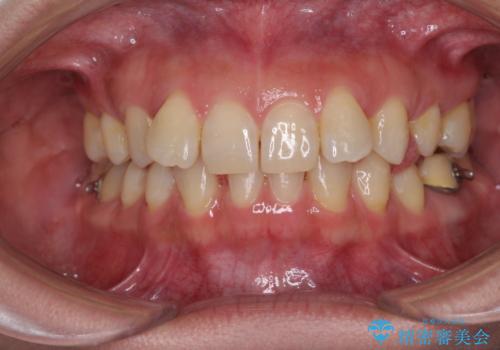

下顎2前歯の欠損 インビザラインによる抜歯矯正

- 下顎前歯欠損による歯列不正を気にして来院された患者様です。

下顎の歯列が小さく、下顎前歯が隠れてしまう過蓋咬合(ディープバイト)であったため、

①下顎歯列を拡大し、欠損部に2歯分のインプラント補綴をおこなう

②上顎左右第一小臼歯2本を抜歯、下顎歯列を拡大し、欠損部に1歯分のインプラント補綴をおこなう

③上顎左右第一小臼歯2本を抜歯し、下顎はスペースを閉じる

のいずれかを提案しました。(①から③の順番にお勧めのプランとなります)

いずれもワイヤー矯正が望ましい治療方法ですが、家が遠方であり、近い将来出産される予定もあるとのことで、何とかマウスピース矯正でも対応可能な③にて治療を行うこととしました。

マウスピースでの抜歯矯正特有の抜歯スペースに向かって奥歯が傾斜する動きが顕著に表れ、ディープバイトは改善されませんでした。

前歯のみが強く接触し、奥歯で咬めない期間も続いたため、ワイヤー装置などを補助的に使用し、何とか終了させることができました。